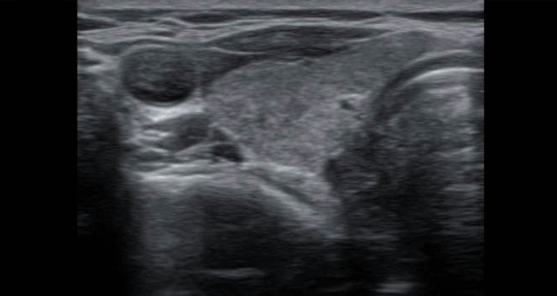

우선, 초음파검사를 다시 합니다. 초음파검사는 상당히 주관적인 검사라서 검사자마다 혹은 검사 때마다 크기 측정의

오차가 생길 수 있습니다. 갑상선암을 다양한 각도에서 여러 차례 측정해서

크기를 확인하여 기록해 둡니다. 이때 갑상선암의 크기, 위치, 주변 침범 등 관찰이 적합하지 않은 경우 수술을

권합니다.

초음파검사 때는 갑상선뿐 아니라 목의 전반적인 림프절의 상태를 확인하고 기록해 둡니다.